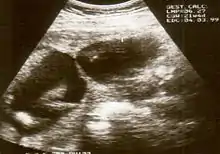

التصوير بالموجات فوق الصوتية

السونار أثناء الحمل قد يفيد في اكتشاف المتلازمة